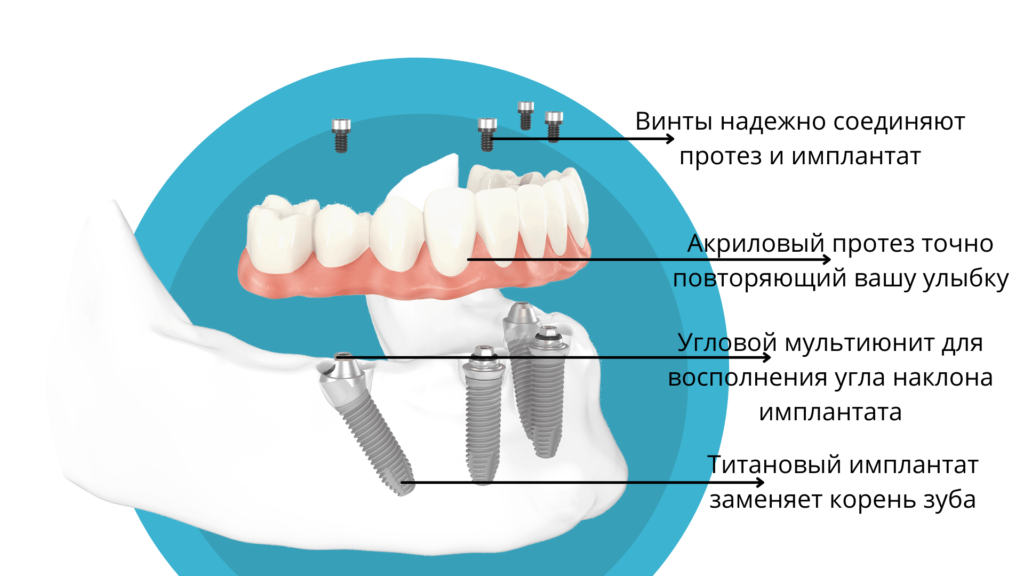

Пошаговое руководство по установке съёмного протеза на импланты